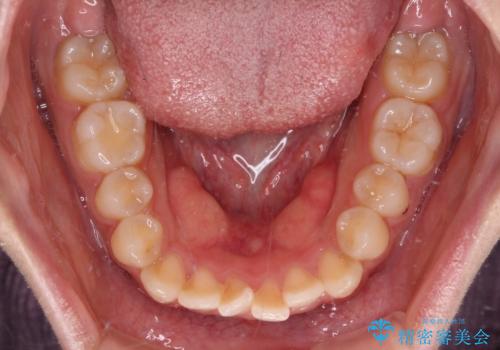

- 前歯のデコボコを気にして来院された患者様です。

マウスピース矯正のような自己管理の煩わしさがなく、早く治療を終えたいとのことで、ワイヤー装置による矯正治療を行うこととしました。